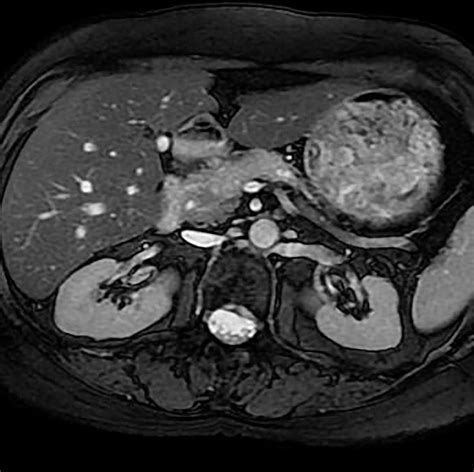

• Magnetic Resonance Imaging (MRI): MRI uses magnetic fields and radio waves to create detailed images of the body. It can provide more information about soft tissues and is often used in conjunction with CT scans.

These advanced imaging techniques can complement the information provided by a Pancreatic Adenocarcinoma CT Scan, helping to create a comprehensive picture of the cancer's extent and characteristics.

Pancreatic adenocarcinoma is a particularly aggressive form of pancreatic cancer that originates in the exocrine cells of the pancreas. Early detection and accurate diagnosis are crucial for effective treatment. One of the most important diagnostic tools for pancreatic adenocarcinoma is the Pancreatic Adenocarcinoma CT Scan. This imaging technique provides detailed images of the pancreas and surrounding tissues, helping healthcare professionals to identify tumors, assess their size and location, and plan appropriate treatment strategies.

After the Pancreatic Adenocarcinoma CT Scan, a radiologist will review the images to look for any signs of pancreatic adenocarcinoma. The results will be sent to the referring physician, who will discuss them with the patient. The scan results can provide valuable information, including:

• The presence and location of any tumors.

• The size and shape of the tumor.

• Whether the tumor has spread to nearby organs or lymph nodes.

• Any other abnormalities in the pancreas or surrounding tissues.